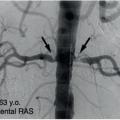

Sténose bilatérale des artères rénales

La répétition d’OAP flash (brutaux) avec poussées hypertensives associée à un déclin de la fonction rénale doit faire rechercher une sténose bilatérale des artères rénales liée essentiellement à l’athérosclérose – plus rarement à une dysplasie fibromusculaire– (fig. 2 ) chez des patients volontiers polyartériels, ou bien un rétrécissement de l’artère rénale sur un rein unique fonctionnel chez les plus jeunes. En effet, dans ces deux situations où l’excrétion de sodium est fortement diminuée, une ischémie rénale s’installe, provoquant un hyper- réninisme avec hyperaldostéronisme secondaire, qui s’accompagne rapidement d’une hypervolémie. L’HTA est dite volodépendante et n’est plus sensible aux bloqueurs du SRAA. Ainsi, toute surcharge hydrosodée, prise d’AINS ou interruption de traitement diurétique peut très rapidement conduire à un OAP.

L’échographie doppler des artères rénales est un moyen simple d’objectiver la ou les sténoses, et surtout d’identifier un retentissement hémo- dynamique d’aval. Un angioscanner peut également être pratiqué si la fonction rénale le permet, mais il ne fournit pas de renseignement d’ordre hémo- dynamique. C’est un point important car, dans certains cas, après avis spécialisé en staff médico-chirugical, une angioplastie d’une artère rénale est parfois réalisée, surtout si l’atteinte est ostiale. Cela peut s’avérer efficace pour contrôler l’HTA, prévenir les récidives d’OAP et peut-être aussi le déclin de la fonction rénale.5